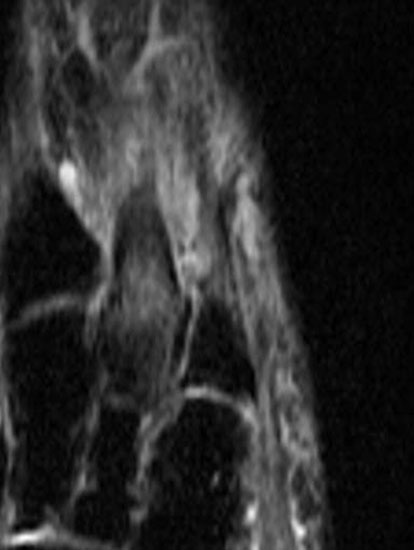

Stoßwellentherapie bei osteochondralen Läsionen

Die Osteochondrosis dissecans tali (OD) ist definiert als lokalisierte Pathologie der Gelenkfläche des Talus, die zur Abtrennung eines kartilaginären Fragmentes und subchondralen Knochens führen kann 93. Es existieren am Körper 3 Prädilektionsstellen für die Entwicklung einer OD mit unterschiedlicher Häufigkeit: Femurkondylen 75%, Talus 12% und Capitulum humeri 12%, sowie sonstigen Lokalisationen 1%. Abhängig vom Zeitpunkt des Auftretens unterscheidet man die juvenile Form (offene Wachstumsfuge) von der adulten Form (geschlossene Wachstumsfuge) (Dotti 2002).

Nach Dotti sind am Talus vorrangig die posteromediale und die anterolaterale Talusschulter betroffen. Die Ätiologie der OD an der anterolateralen Talusschulter scheint vermehrt traumatisch/repetitiv mikrotraumatisch zu sein, die der posteromedialen Talusschulter vermehrt idiopathisch.

Die Stadieneinteilung nach Berndt und Harty umfasst 4 Stadien und ist unabhängig von der Lokalisation der OD anwendbar 94.

Die Stadieneinteilung nach ARCO (Association Internationale de Recherche sur la Circulation Osseuse) berücksichtigt die Kombination aus MRI-Zeichen, Nativradiologie und Knochenszintigraphie 95.

Als Alternative zu operativen Maßnahmen wird bei frühen Stadien der OD auch der Einsatz fokussierter Stoßwellentherapie diskutiert, wenngleich es bislang wenig klinische Studien zur ESWT bei OD am Talus gibt.

Die ESWT wird in der Regel in einer Sitzung unter Leitungs– oder Allgemeinanästhesie durchgeführt, wobei nach Empfehlungen der DIGEST eine mittlere Energieflussdichte von 0,35mJ/mm² und eine Anzahl von 2500 Impulsen empfohlen wird. Bei hochenergetischer Behandlung (>0,5mJ/mm²) kann eine Schädigung des Knorpels nicht sicher ausgeschlossen werden 97.

Nach der Behandlung wird eine Entlastung für ca. 2 - 6 Wochen empfohlen. MRT-Kontrollen sind nach 3, 6 und 12 Monaten sinnvoll.

Aufgrund der Datenlage kann die Anwendung der ESWT bei osteochondralen Läsionen des Talus in frühen Stadien (1 und 2 nach ARCO) erwogen werden. Für eine Therapieempfehlung sind allerdings weitere Studien, insbesondere zur Therapie der OD des Talus zwingend erforderlich. Aufgrund der technischen Schwierigkeit der Behandlung bei teilweise schlechter Erreichbarkeit der Läsion, sollte diese Indikation erfahrenen Anwendern vorbehalten bleiben.